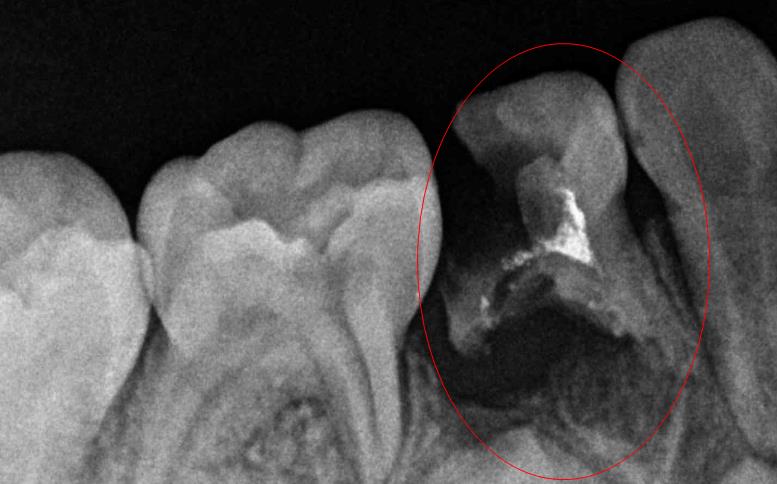

嚴(yan) 重齲壞的牙齒拍片的情況

蛀牙顯現出來的症狀和反應通常隻是判斷蛀牙基礎的方法,實際上進一步確診,以及齲壞到什麽(me) 地步,是否嚴(yan) 重,通常都需要結合牙片才能做出準確的判斷。

有的蛀牙看著外麵黑色陰影很大,但是其實裏麵很小,就像一個(ge) 倒三角形一樣;而有的蛀牙看著外麵陰影很小,但是裏麵壞得大,就像個(ge) 正三角形一樣。

而且蛀牙壞到牙齒表層的牙釉質還是裏層的牙本質,或者是中間的牙髓組織,這都要拍片才能知道的,而且齲壞到不同的牙齒位置,治療方法也不相同。